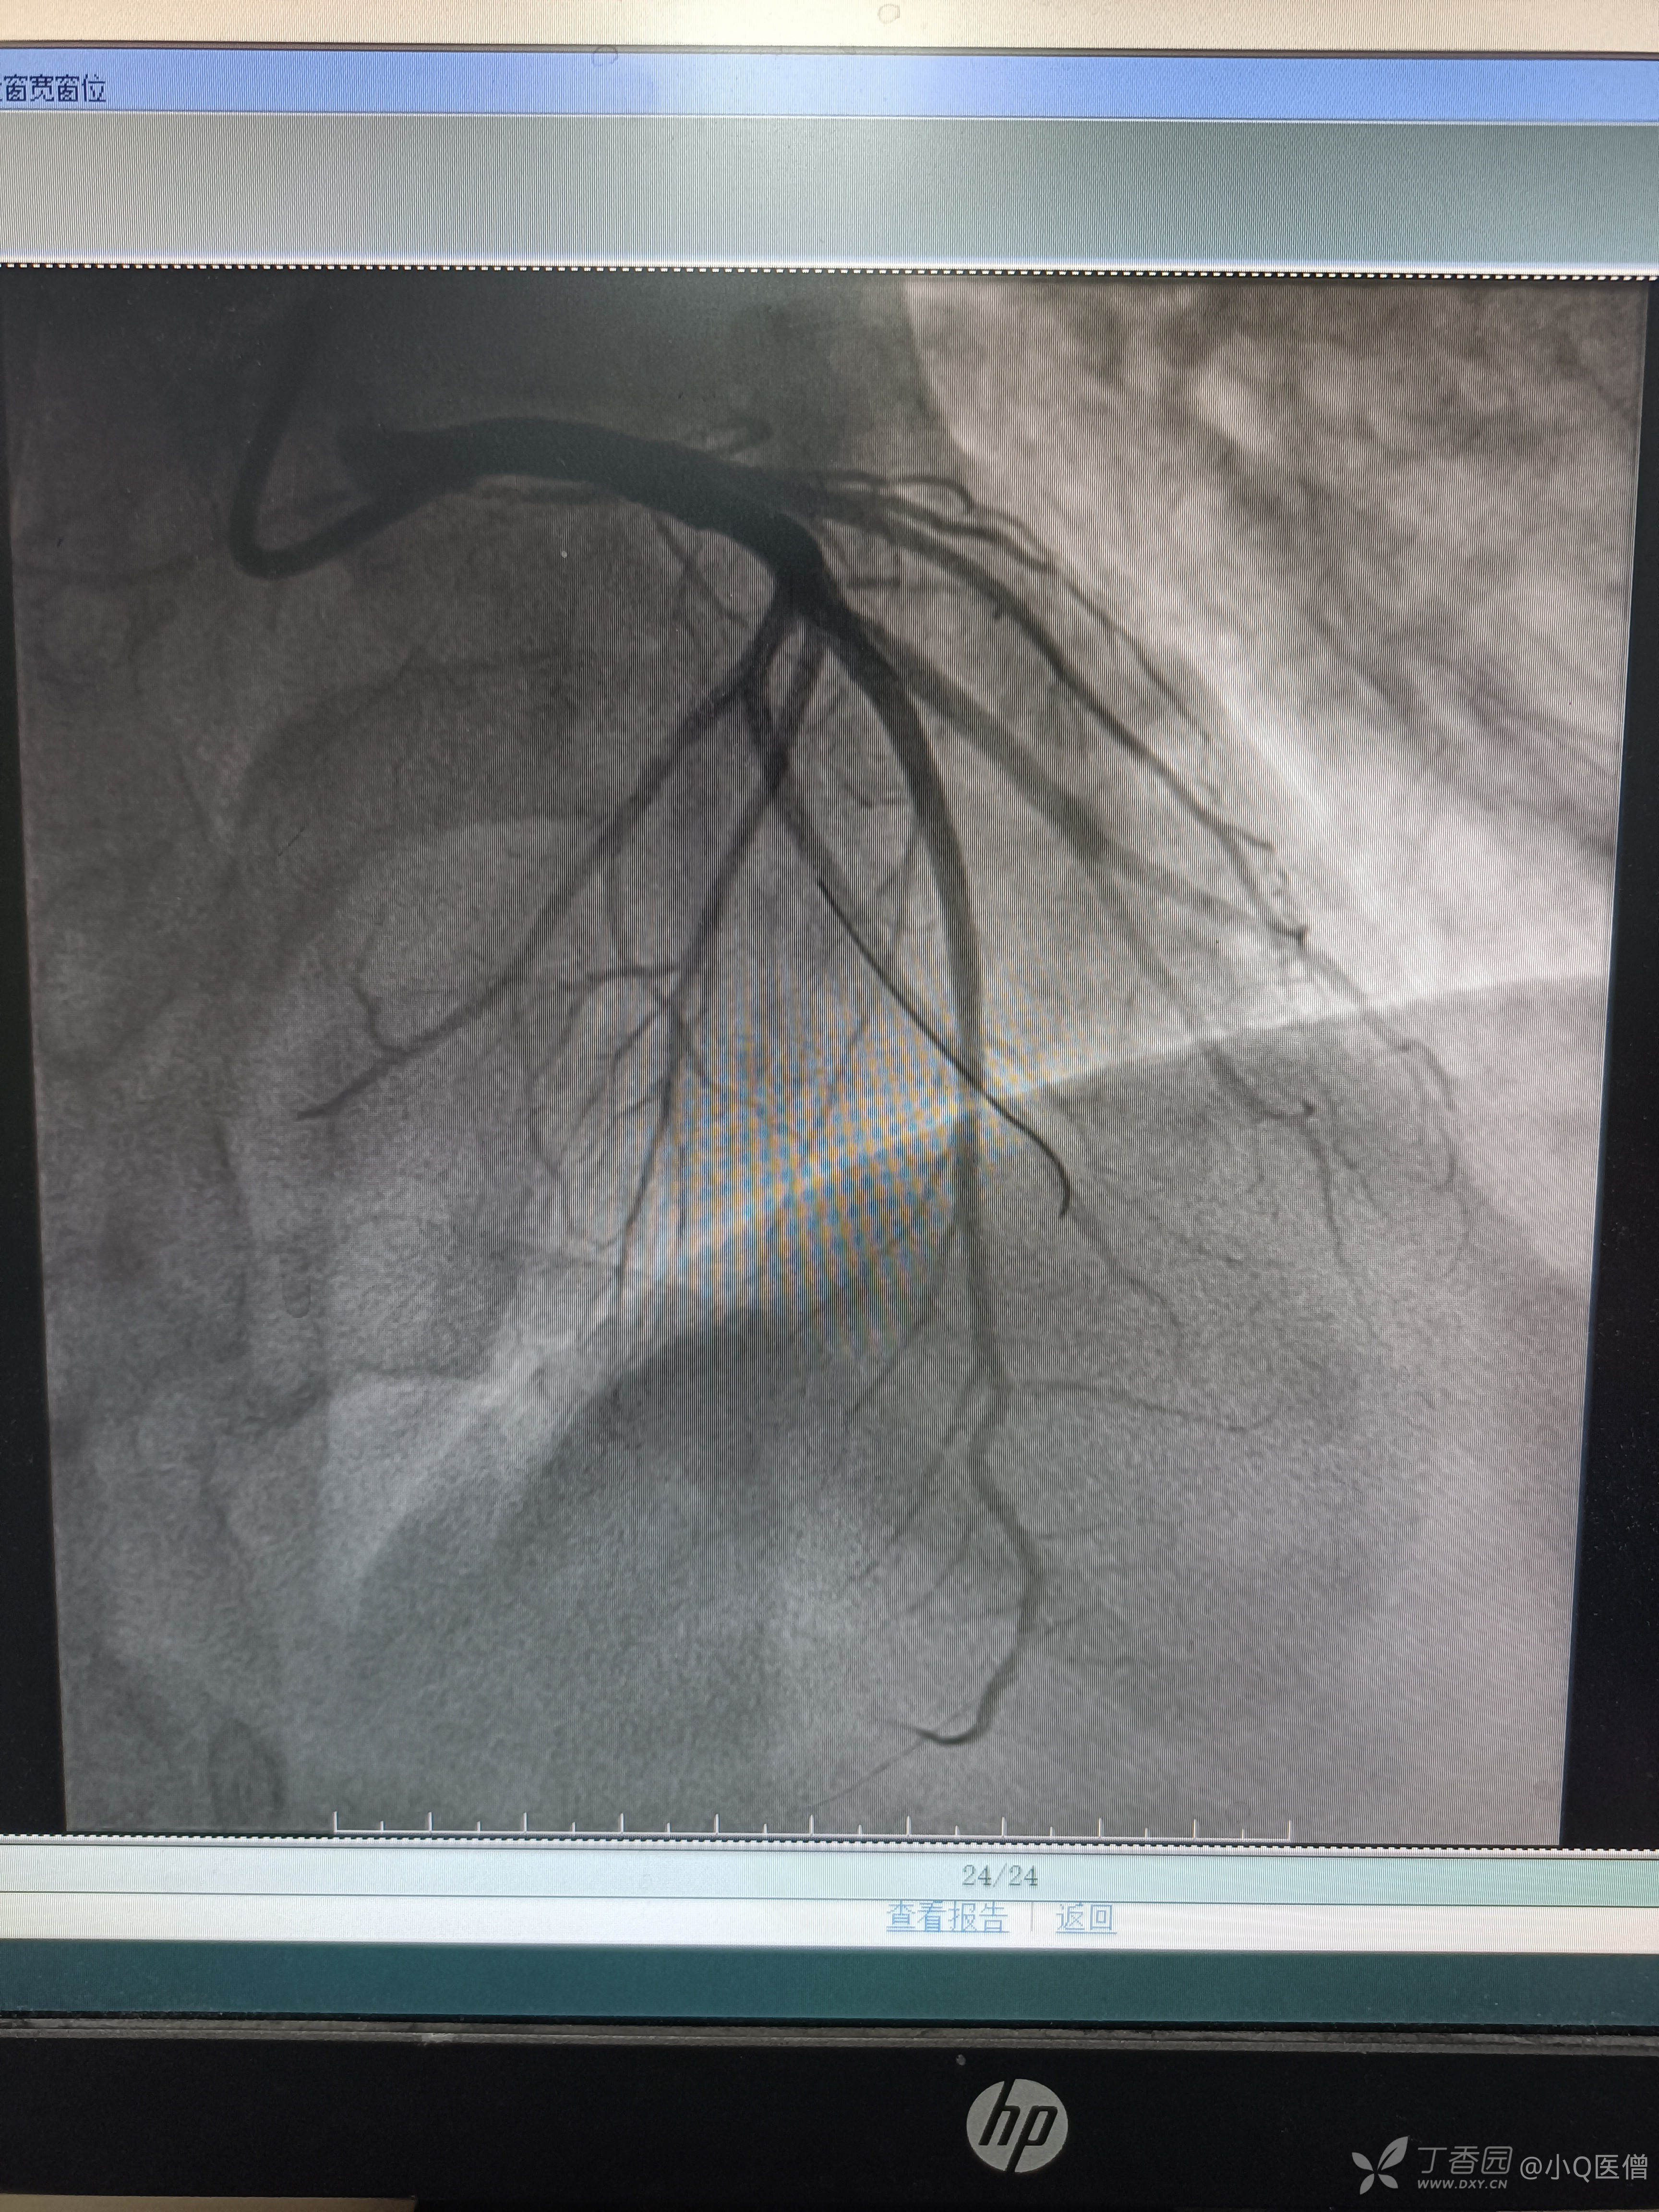

心肌标志物示肌钙蛋白I升高,肌红、CK-MB正常,考虑急性心梗,给予双抗负荷后急P,造影结果如下:

开通后置入心祥3.0*18mm支架一枚,